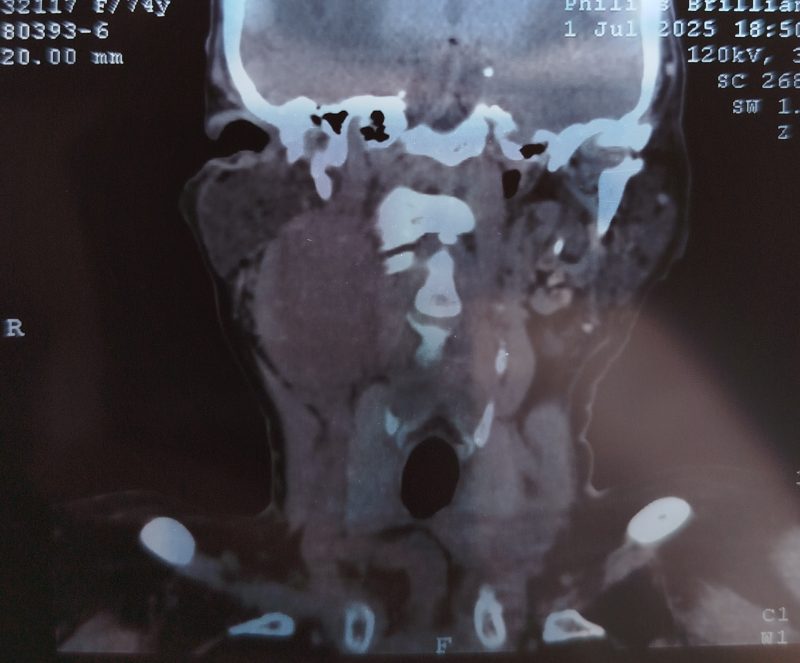

Пациент К. 1950 гр. Поступил в ООГШ 26.08.2025 с жалобами на новообразование шеи справа. Считает себя больным около 6 лет. В поликлинику по месту жительства обратился в июне 2025г. В рамках обследования было проведено МРТ шеи: В проекции каротидного и заднего шейного пространства визуализируется объёмное образование с четкими бугристыми контурами, размерами до 45х36х49 мм, с признаками интенсивного равномерного накопления контрастного вещества, с признаками ограничения диффузии. Внутренняя сонная артерия справа огибает образование, яремная вена на уровне образования достоверно не прослеживается- вероятно вовлечена в процесс. МР-картина объемного образования сосудистого и заднего шейного пространств шеи справа с вовлечением яремной вены? Направлен в БУЗ ВО «ВОНКОЦ» для уточнения диагноза. В поликлинике БУЗ ВО ВОНКОЦ выполнена ТИАБ (тонкоигольная аспирационная биопсия) образования шеи справа. Цитологическая картина — клетки атипии, дистрофии. Госпитализирован в отделение ООГШ для проведения хирургического лечения с целью установки морфологической верификации.

27.08.2025 было проведено удаление опухоли мягких тканей шеи справа. При ревизии выявлена опухоль мягких тканей 5х6 см, тесно прилежащая к общей сонной артерии, окруженная множеством мелких сосудов. Внутренняя яремная вена и подъязычный нерв тесно спаяны и входят в состав опухоли, включены в блок удаленных тканей. С большими техническими трудностями при повышенной кровоточивости опухоль выделена и удалена. Операция прошла успешно. Пациент переведен в палату. Активизирован в течение первых суток.

При гистологическом исследовании- морфологическая картина параганглиомы. При проведении иммуногистохимии был установлен злокачественный характер опухоли.